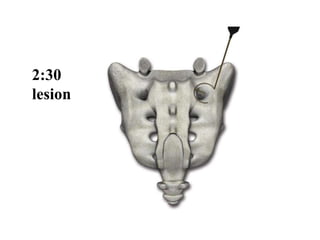

Lesion Geometry

Lesions 8-10 mm from lateral edge of foramen

Target sites should be 50° apart (1:40 on the clock) to

achieve overlap

2:30

lesion

4:00

5:30

At S2

2:30,

4 and

5:30 lesions

At S3

2:30 and

4:00 lesions